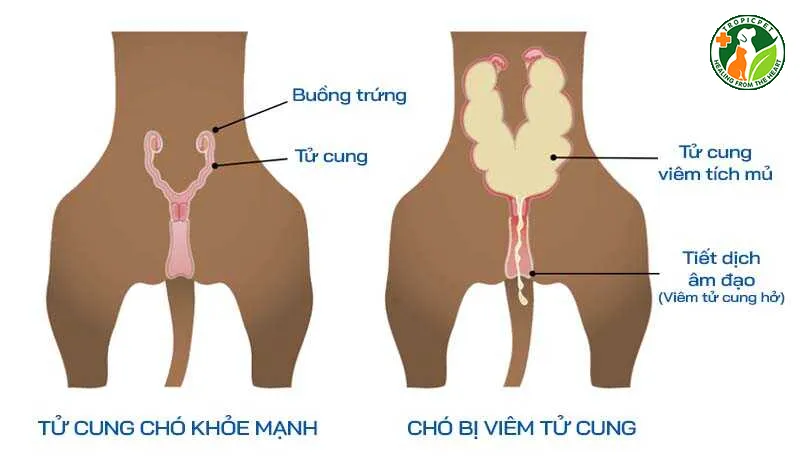

Viêm tử cung ở chó hay còn được gọi là Pyometra trong thuật ngữ y khoa quốc tế. Đây là một bệnh lý nhiễm trùng tử cung cấp tính hoặc mãn tính gây nguy hiểm nghiêm trọng.

Tình trạng chó bị viêm tử cung thường được chia làm hai dạng chính dựa trên trạng thái cổ tử cung. Viêm tử cung dạng hở là trường hợp cổ tử cung của chó vẫn mở một phần hoặc toàn bộ.

Dấu hiệu đặc trưng nhất của dạng này là dịch mủ chảy ra từ âm đạo có màu vàng, xanh hoặc nâu. Dịch tiết thường có mùi hôi nồng nặc và dính bết vào lông xung quanh vùng sinh dục của chó.

Viêm tử cung dạng kín là trường hợp nguy hiểm hơn do cổ tử cung đóng chặt hoàn toàn. Khi đó, toàn bộ dịch mủ và độc tố bị giữ lại bên trong tử cung và không thể thoát ra.

Do mủ không thoát ra ngoài, áp lực bên trong tử cung tăng cao khiến bộ phận này sưng to nhanh chóng. Bụng của chó sẽ phình to rõ rệt và con vật thường xuyên tỏ ra đau đớn dữ dội.